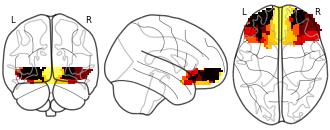

Connectivity-Based Parcellation of the Human Orbitofrontal Cortex: K=2...

EmailClick to copy linkLink copied Cite(2024). Connectivity-Based Parcellation of the Human Orbitofrontal Cortex: K=2 cluster map [Dataset]. http://identifiers.org/neurovault.image:887623niftiAvailable download formatsUnique identifierhttps://identifiers.org/neurovault.image:887623Dataset updatedNov 18, 2024License

Cite(2024). Connectivity-Based Parcellation of the Human Orbitofrontal Cortex: K=2 cluster map [Dataset]. http://identifiers.org/neurovault.image:887623niftiAvailable download formatsUnique identifierhttps://identifiers.org/neurovault.image:887623Dataset updatedNov 18, 2024LicenseCC0 1.0 Universal Public Domain Dedicationhttps://creativecommons.org/publicdomain/zero/1.0/

License information was derived automaticallyDescriptionK=2 cluster map based on N=13 participants.

Collection description

K-means cluster maps of orbitofrontal cortex with K=2, 3, 4, 5, 6, and 7 clusters based on resting-state fMRI data.